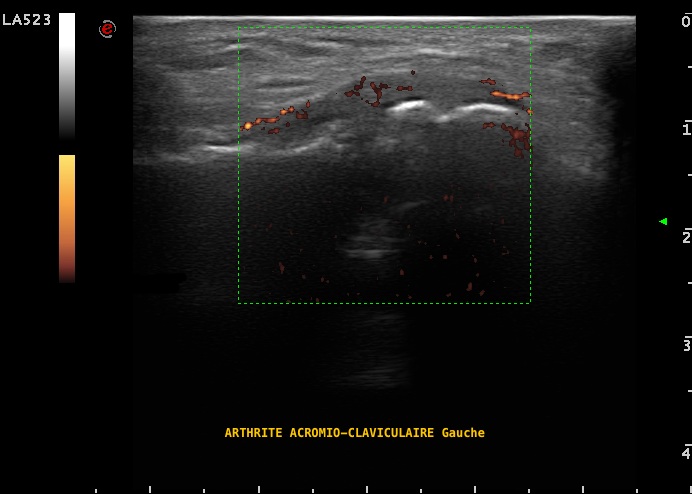

Arthrite acromio-claviculaire gauche en échographie, dans le cadre d'une infection à pyogène